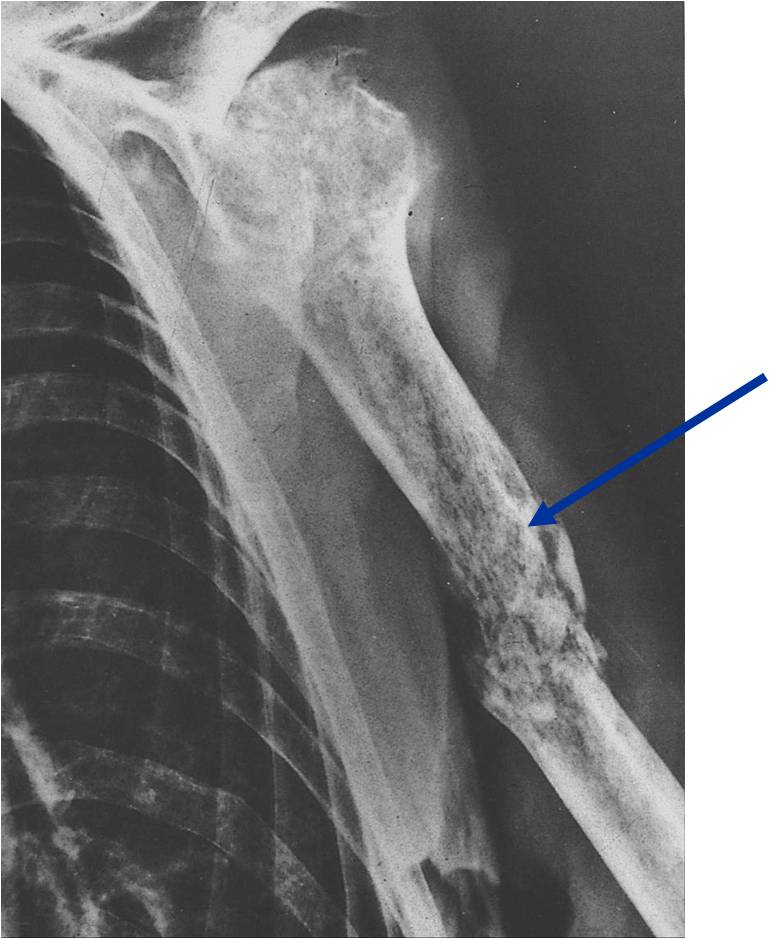

Fibromul condromixoid se poate prezenta cu fractura patologica. Una frattura patologica è un osso rotto causato da una malattia, piuttosto che da una lesione.

December 2019 · revista espanola de cirugia oral y maxilofacial. Un detonante puede hacer que el hueso se rompa, puede ser por. Vi mostro il quadro tac di una frattura patologica della quarta vertebra lombare. Definitie o fractura patologica este aceea care apare spontan, in cursul unei activitati de rutina pe care persoana afectata. O fractură patologică este o fractură osoasă cauzată de slăbiciunea structurii osoase care duce la scăderea rezistenței mecanice la sarcini mecanice normale. December 2019 · revista espanola de cirugia oral y maxilofacial. La frattura patologica è una frattura che si verifica senza la partecipazione di un trauma sufficiente in genere a provocarla. Doctors, medical centers and hospitals experts on frattura patologica that you can contact, take appointment or send examination results. Come ti abbiamo anticipato, la frattura corrisponde alla rottura di un particolare segmento. Se la frattura riguarda solo l'osso è detta isolata, mentre se coinvolge anche i legamenti è detta associata. Il punto preciso di interruzione è detto rima di. Download scientific diagram | frattura patologica da metastasi di carcinoma renale. Una frattura patologica è una frattura ossea causata dalla debolezza della struttura ossea che porta a diminuire la resistenza meccanica ai normali carichi meccanici. Frattura patologiche e impending fracture. En la clínica diaria podremos encontrar un tipo de fractura que no es traumática sino patológica, y al evaluar las radiografías debemos detallar 4 factores. Una frattura patologica è un osso rotto causato da una malattia, piuttosto che da una lesione. Un'ulteriore distinzione è quella tra fratture fisiologiche e patologiche.